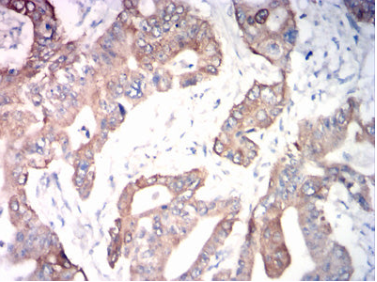

ADAM10 Mouse Monoclonal antibody[6C3C7]

IHC    1/200-1/1000